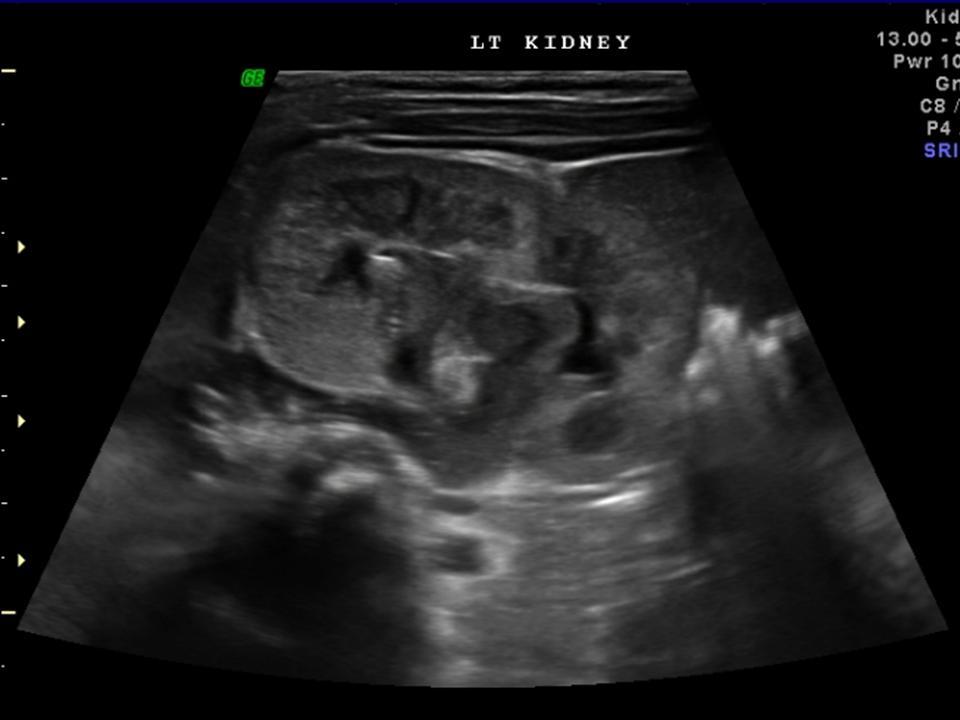

What is this?

What are the imaging features?

Imaging Features of Calyceal Diverticulum

Figure 4

A 50-year-old female with left flank pain. (a) Two radiographs from an intravenous urogram (IVU) study: 20 min (left) and post-micturition (right). The images demonstrate contrast opacifying a lower pole calyceal diverticulum containing numerous calculi (arrow). Further opacification of the diverticulum is evident on the later film (right-hand image; arrow), highlighting the need for delayed images. Note that the infundibulum cannot be seen on either radiograph. (b) Coronal and transverse images from an MR urogram identify the lower pole calyceal diverticulum on the left side (arrow). Multiple areas of low signal are identified within the diverticulum and correspond to calculi (arrow).